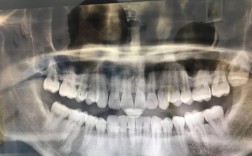

智齿阻生或位置异常

X光片显示智齿完全埋伏于骨内、部分萌出但与邻牙形成角度(如近中倾斜、水平阻生),或已压迫第二磨牙牙根,导致牙根吸收、邻牙松动,这类智齿不仅无法正常发挥作用,还会成为矫正中的“隐患”,建议在矫正前拔除。 -